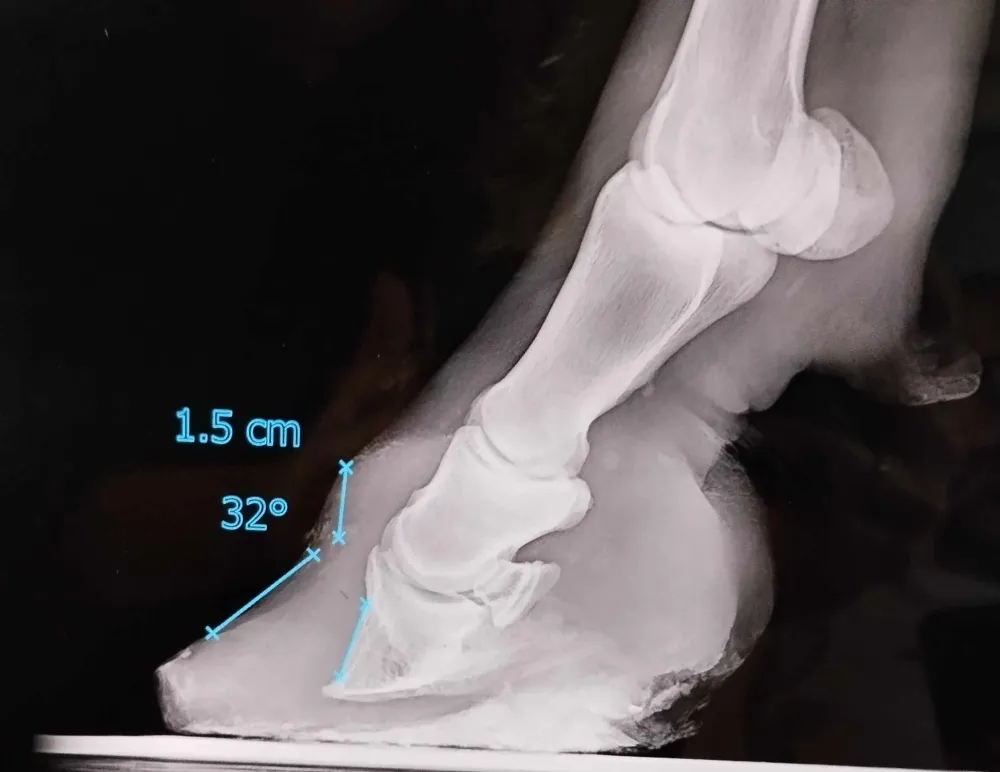

Radiographie de pied de poney fourbu présentant une bascule de la troisième phalange Zoomer

La fourbure correspond à une inflammation et une modification de la vascularisation du pied. Ces modifications causent une séparation des deux couches du sabot (kéraphylle et podophylle) ainsi qu'une bascule et éventuellement une descente de la troisième phalange contenue dans le pied.

La réalisation de radiographies de pieds permets d'évaluer la gravité de la fourbure et permet d'effectuer une prise en charge appropriée.